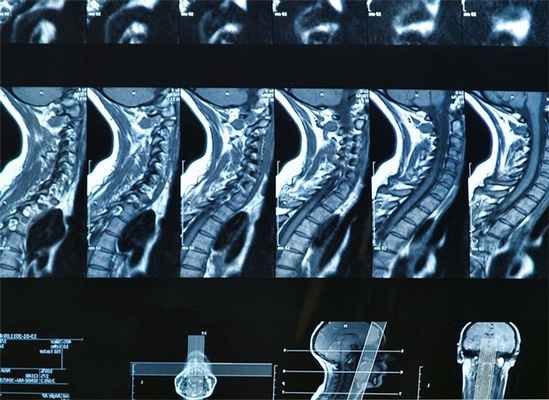

Магнитно-резонансная томография предоставляет множество снимков, сделанных в разных плоскостях, что позволяет заметить даже скрытые патологии.

Получив с помощью МРТ-исследования серию срезов, врач оценивает изображение отделов позвоночника в 3х взаимно перпендикулярных проекциях. При магнитно-резонансной томографии (МРТ) позвоночника визуализируются тела позвонков, межпозвонковые диски, суставы, спинной мозг, а так же нервные корешки, выходящие из спинномозгового канала.